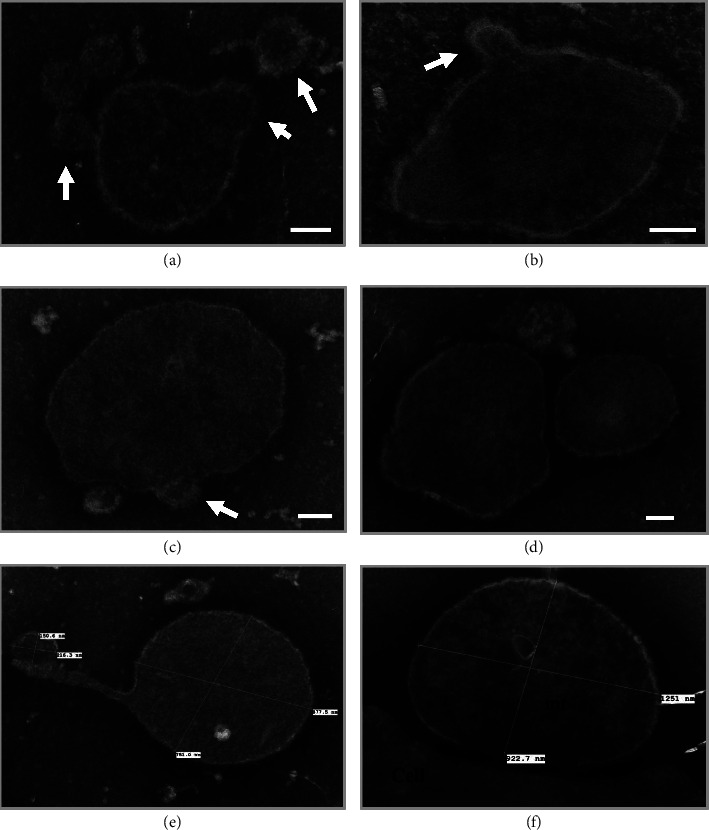

Myalgic encephalomyelitis/chronic fatigue syndrome (ME/CFS) is a multisystem disabling disease with unclear etiology and pathophysiology, whose typical symptoms include prolonged debilitating recovery from fatigue or postexertional malaise (PEM). Disrupted production of adenosine triphosphate (ATP), the intracellular energy that fuels cellular activity, is a cause for fatigue. Here, we present a long-term case of ME/CFS: a 75-year-old Caucasian female patient, whose symptoms of ME/CFS were clearly triggered by an acute infection of the Epstein-Barr virus 24 years ago (mononucleosis). Before then, the patient was a healthy professional woman. A recent DNA sequence analysis identified missense variants of mitochondrial respiratory chain enzymes, including ATP6 (ChrMT: 8981A > G; Q152R) and Cox1 (ChrMT: 6268C > T; A122V). Protein subunits ATP6 and Cox1 are encoded by mitochondrial DNA outside of the nucleus: the Cox1 gene encodes subunit 1 of complex IV (CIV: cytochrome c oxidase) and the ATP6 gene encodes subunit A of complex V (CV: ATP synthase). CIV and CV are the last two of five essential enzymes that perform the mitochondrial electron transport respiratory chain reaction to generate ATP. Further analysis of the blood sample using transmission electron microscopy demonstrated abnormal, circulating, extracellular mitochondria. These results indicate that the patient had dysfunctional mitochondria, which may contribute directly to her major symptoms, including PEM and neurological and cognitive changes. Furthermore, the identified variants of ATP6 (ChrMT: 8981A > G; Q152R) and Cox1 (ChrMT: 6268C > T; A122V), functioning at a later stage of mitochondrial ATP production, may play a role in the abnormality of the patient's mitochondria and the development of her ME/CFS symptoms.